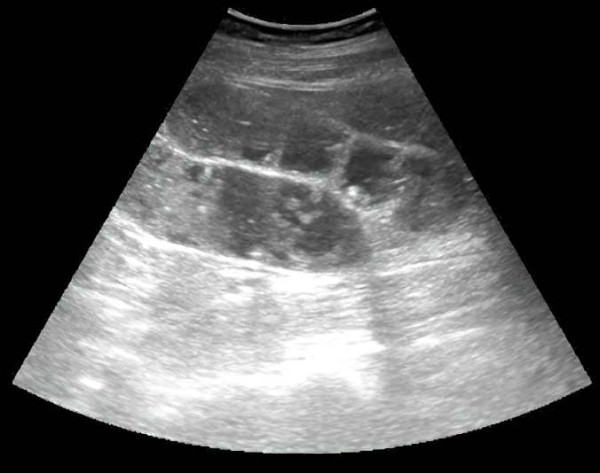

Из протокола УЗИ: «В правой подвздошной области визуализируется слепо заканчивающийся, не перистальтирующий участок кишки 7 мм в диаметре,

наполненный жидкостью, болезненный при компрессии датчиком» (см. рис. 7).

Рисунок 7. Картина УЗИ при флегмонозном аппендиците.